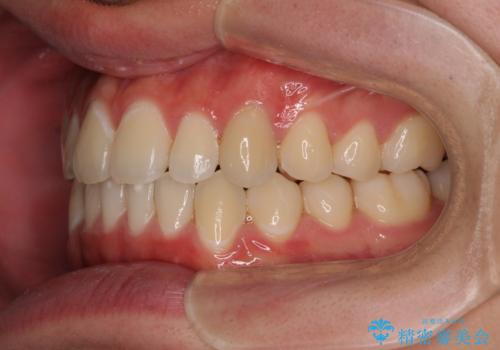

受け口傾向の咬み合わせ インビザラインできれいな口元に

- 前歯のデコボコを治したいとのことで来院された患者様です。

受け口傾向の骨格であり、前歯はクロスバイトまたは切端咬合となっており、叢生は警備であったため、下顎を中心に歯列全体の後方移動を行い、IPR(歯と歯の間を削る)によってデコボコが解消するように設計し、インビザラインにより治療を行うこととしました。

受け口傾向のインビザライン矯正は比較的治療を行いやすいため、きれいに仕上げることができました。舌の突出癖が顕著であったため、改善のためのトレーニングをしっかりと行っていただきました。